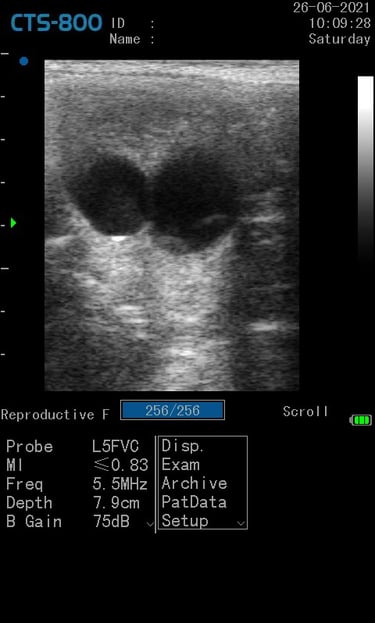

Gynécologie